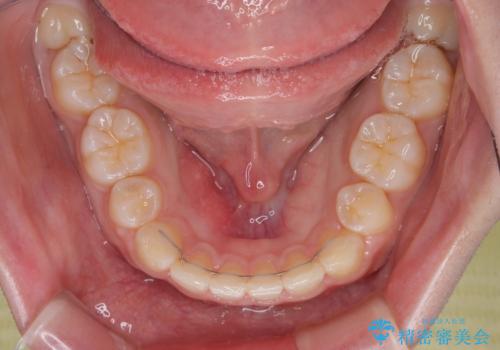

抜歯矯正を行ったことで、顎先のつっぱり感や口元の閉じにくさを解消することができました。

- 出っ歯と口の閉じにくさ、デコボコを気にして来院された患者様です。

口元の突出感を改善するため、上下左右第一小臼歯4本の抜歯を行い、ワイヤー装置による矯正治療を行うこととしました。